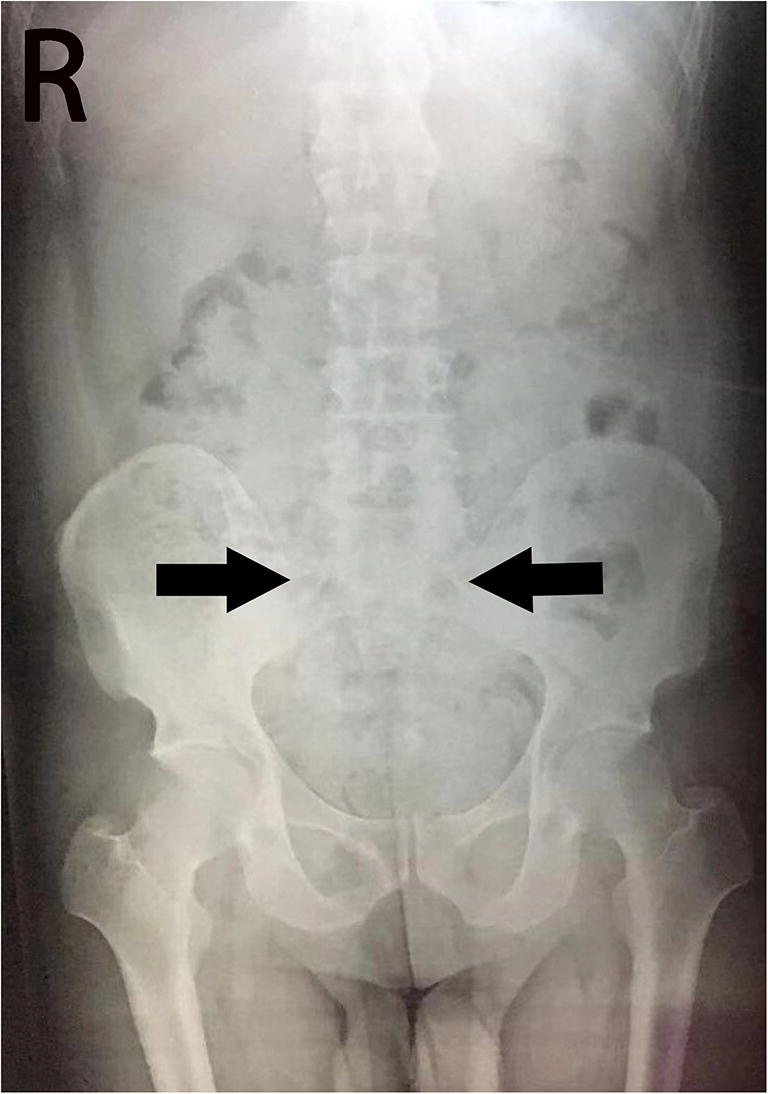

Laboratory blood testing, including routine blood tests, routine biochemical evaluations, and tests for rheumatoid factors and rheumatological autoantibodies (anti-cyclic citrullinated peptides antibodies, anti-nuclear antibodies, anti-double-stranded DNA antibodies, anti-ENA autoantibody profile, and antiphospholipid antibodies); thyroid profile (triiodothyronine, thyroxine, thyroid-stimulating hormone); tumor biomarkers (prostate-specific antigen (PSA) and α-fetoprotein (AFP), carcinoembryonic antigen (CEA), carbohydrate antigen (CA)125, CA19-9, CA724); treponema pallidum; and viral serological tests (herpes simplex virus 1/2, human immunodeficiency virus, human cytomegalovirus, and Epstein-Barr virus) were all negative or normal, except for C-reactive protein, which was 25 mg/L (normal value < 5 mg/L). A genetic study revealed that the patient was HLA-B27-positive (flow cytometry) (Supplemental Fig. 1). CT scans of the abdomen and chest conducted upon this admission to detect an underlying tumor revealed no tumor signs. Fluid-attenuated inversion recovery and T1- and T2-weighted magnetic resonance imaging (MRI) of the patient’s brain were unremarkable (Supplemental Fig. 2 A–C). An electroencephalogram (EEG) documented a frontal slowing wave but without epileptic discharge (Supplemental Fig. 2 D–E). A spinal X-ray showed hyperosteogeny of the spine and narrowing of the lumbar intervertebral space with blurred space in the bilateral sacroiliac joints (Fig. 2). An MRI of the sacroiliac joints revealed narrow spaces between the bilateral sacroiliac joints with rough articular surfaces and abnormal signals below the articular surface, which indicated the possibility of AS. Additional laboratory results are shown in Table 1.

Fig. 2

Spinal X-rays of the patient. Spinal x-rays show bilateral sacroiliitis with blurred articular surfaces (arrows), indicating the possibility of ankylosing spondylitis

Based on the seizures and the abnormal psychiatric symptoms, in addition to the evidence of GABAB-R antibodies detected in the CSF and serum, the patient was diagnosed with anti-GABAB-R encephalitis. Our case also met the diagnostic criteria for AS by the positive HLA-B27 test and manifestations on spine and sacroiliac joint imaging. Reports on the co-occurrence of anti-GABAB-R encephalitis with tumors or another paraneoplastic neurologic disorder, such as Lambert-Eaton myasthenic syndrome, have been published [3]. However, a literature search for reports on anti-GABAB-R encephalitis or AE appearing with AS yielded nothing. Likewise, there were no reports of investigations undertaken to explain the relationship between anti-GABAB-R encephalitis and AE with AS. Some research has suggested that T cell-based autoimmunity plays an important role in the development of anti-GABAB-R encephalitis [4]. Similarly, T cells were found to act in key pathogenetic roles in AS, as well [2]. In addition, interleukin 17 (IL-17) plays a key role in inflammatory pathways and there is an evidence that IL-17 receptor-deficient mice may be protected against experimental AE. Furthermore, inflammatory disorders have also been associated with IL-17, and therapeutically targeting this inflammatory pathway could improve the outcome of AS patients because similar inflammatory pathways may exist between the two diseases [5].